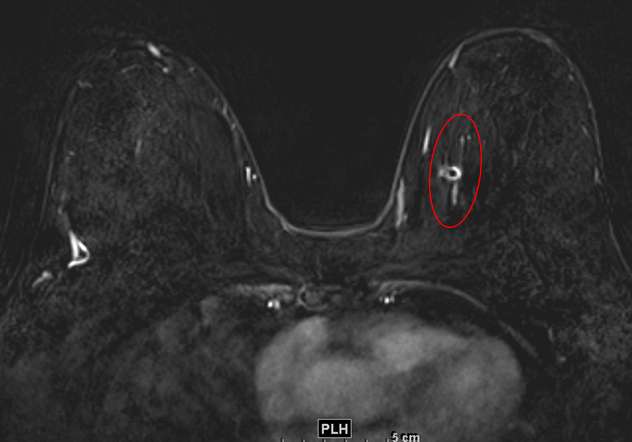

Biopsy-Proven DCIS as Linear, Heterogeneous NME.

Figure 1. Biopsy-Proven DCIS as Linear, Heterogeneous NME. Contrast-enhanced breast MRI, axial subtraction image demonstrates NME in the left breast with linear distribution and heterogeneous enhancement at 9-10 o’clock, spanning 35 mm in anterior-posteri